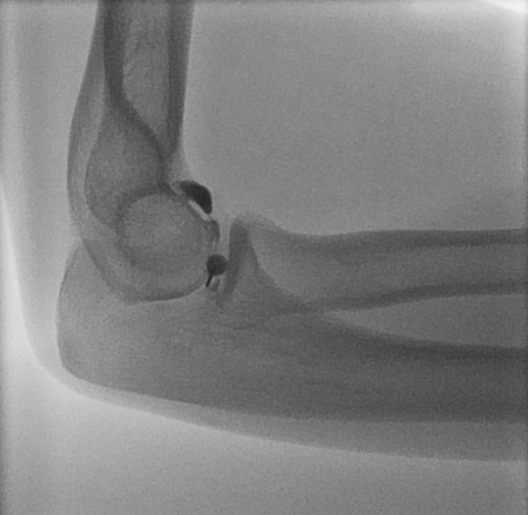

Elbow joint injection